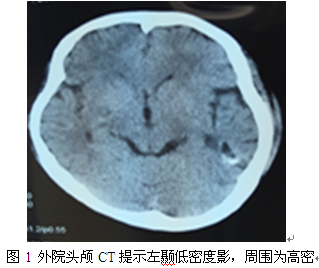

入院诊断:1.症状性局灶性癫癎;2.左颞海绵状血管瘤

经科室讨论分析患者为右利手,语言优势半球侧位于左侧可能性大。结合患者海绵状血管瘤(CM)位于左侧颞中下回后部,与感觉及命名性语言中枢及计算中枢关系密切,进一步详细查体发现患者计算能力存在一定障碍(稍复杂计算题回答错误,家属反映小时读书数学考试成绩明显较差,一直认为患者学习不认真所致)。应进一步完善Wada试验及功能核磁进一步行功能评估。而患者脑电图提示左颞叶痫样放电明显,癫痫与CM关系密切。Wada试验结果提示语言优势半球确实位于左侧,患者有明确手术适应症。手术在导航及术中唤醒下进行,术中主要进行计算及感觉性命名性语言检测,结合皮层电极检测结果(未检测到明显痫样放电)决定切除海绵状血管瘤及含铁血黄素沉积带。患者术中配合良好,预定手术切除范围顺利完成,整个手术过程患者未出现新的功能障碍,原有计算障碍未加重。术后复查核磁共振显示CM及含铁血黄素带切除彻底,病人恢复好。